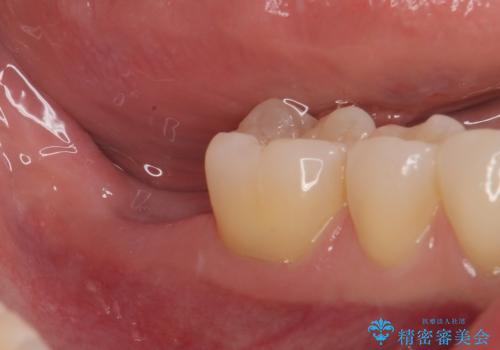

- 奥歯が抜歯となり、インプラント治療を希望して来院された患者様です。

来院時には抜歯して1ヶ月ほど経過していたとのことで、3次元レントゲンよりインプラントの早期埋入が可能と診断されました。

インプラント埋入と同時に仮歯を装着するために、事前に仮歯を用意し、速やかにインプラント埋入を行うこととしました。